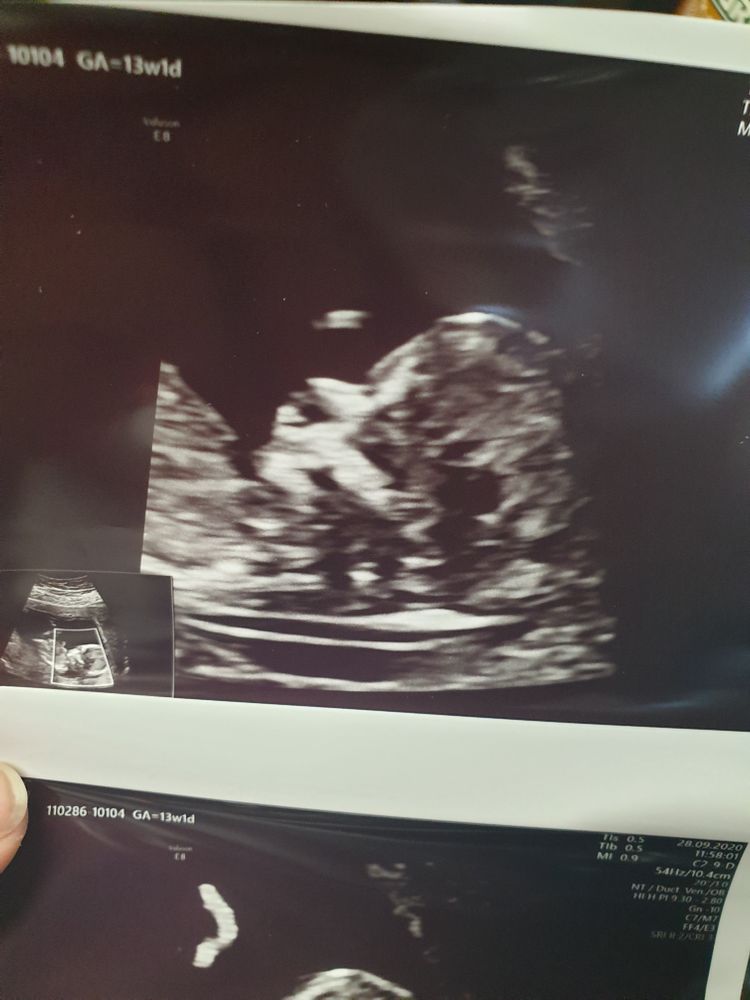

Девочки, сегодня была на первом скрининге 🥰 всё у нас хорошо. Развиваемся точно по сроку 13+3. Я ожидала, что наш сынуля побольше будет, а там полноценный человек уже 🥰🥰🥰

Плацента по передней стенке, малыш 7,7см. Никаких замечаний.

Пальчики пересчитали, сердечко 160 ударов.